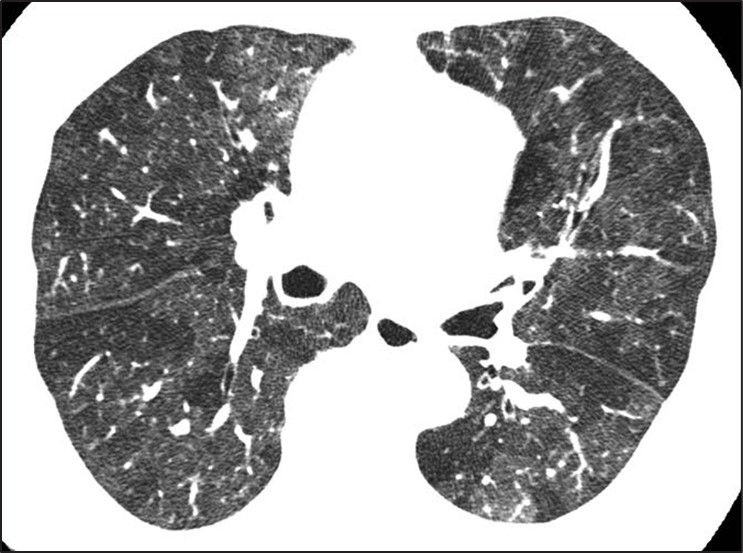

Although many centrilobular nodules may be present in lymphatic diseases, nodules should also be seen in the peribronchovascular or sub- pleural interstitium. This is in distinction to the centrilobular pattern in which only centrilobular nodules are present and no subpleural nodules should be seen. Lastly, diseases typically associated with a perilymphatic distribution of nodules (such as sarcoidosis) may occasionally show a fairly homogeneous involvement of the lung, mimicking a random distribution [27] (Fig. 11).

Fig. 11—Axial high-resolution CT scan shows perilymphatic distribution mimicking random nodules. Innumerable tiny nodules are present. Although pattern resembles random distribution, heterogeneous distribution in lung shows proportionally more nodules along fissures (arrows) than would be expected for random distribution.

A greater number of nodules in the subpleural or peribronchovascular interstitium may be the only clue that the distribution is perilymphatic.